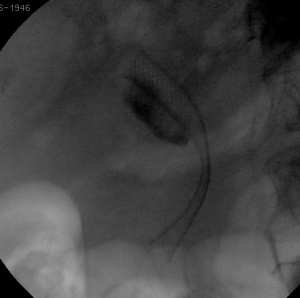

CPRE avec Prothèse biliaire pour cancer du pancréas

L’incidence du cancer du pancréas est en nette progression depuis quelques années. Avec une survie à 5 ans de l’ordre de 1 à 3 % et une survie moyenne de ...